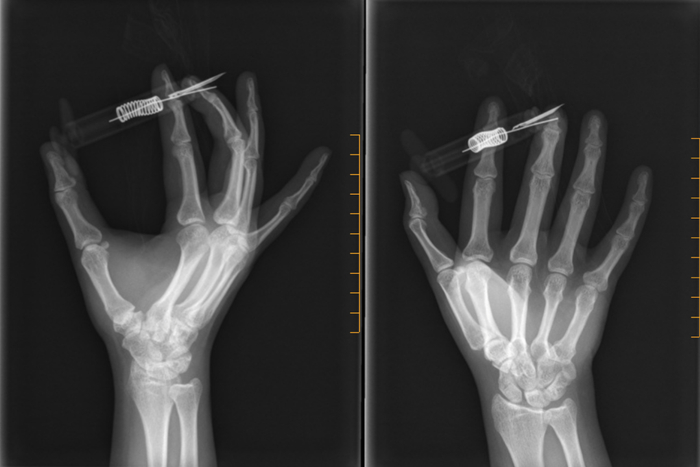

候诊到我了,医生看了一下手,又看了商家网页上的操作视频,只看了一遍就明白了。他让我去拍手部X线片,并让我等报告时,去打破伤风针。我的右手渐渐麻木冰凉,不得不需要另一只手扶着,才能尽量在拍片时保持案发现场原样。

打好针,回到骨科急诊室,大夫在电脑上调出X线片,告诉我异物扎穿了中指骨头,现在需要手术。